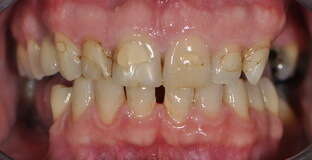

1. Restauration complète maxillaire et mandibulaire